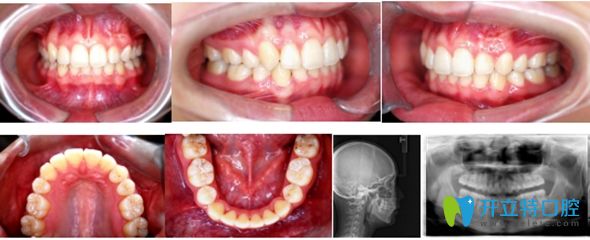

用時20個月,小哥哥矯正結(jié)束,開始佩戴透明保持器。

小哥哥在北京佳美口腔正畸牙齒術(shù)后圖

<小哥哥說:牙齒矯正用痛并快樂形容,太貼切了!效果如上>      ↑↑